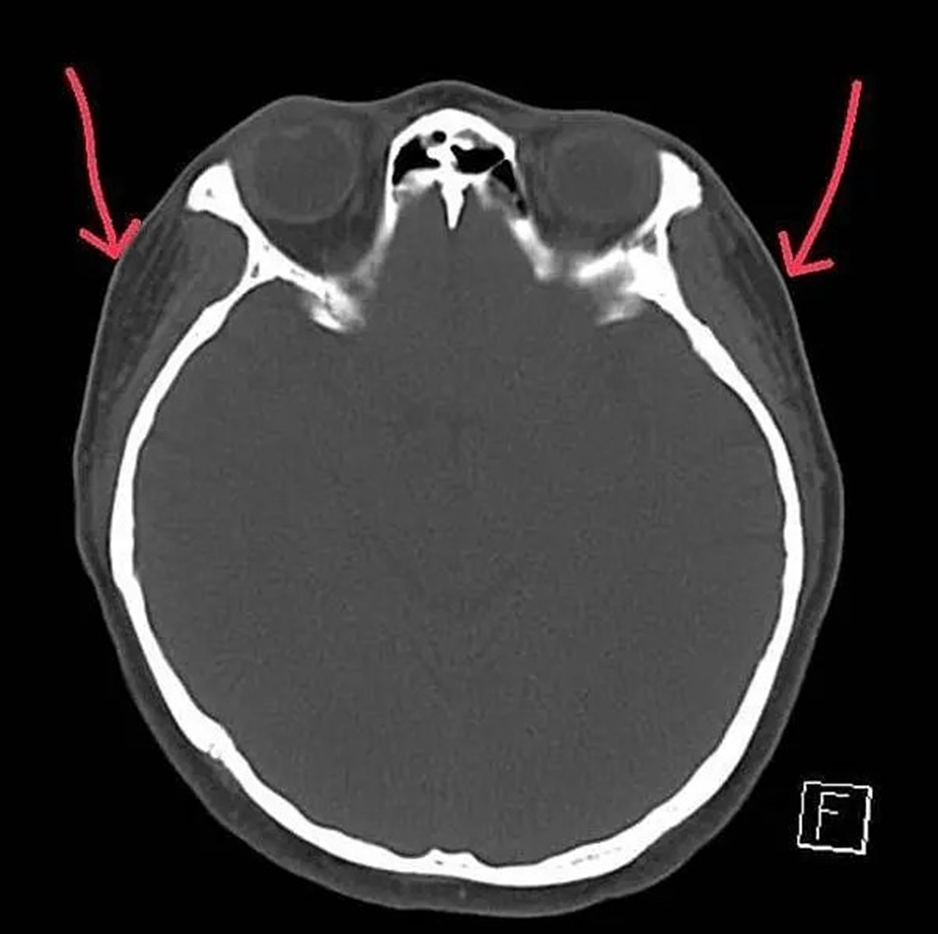

電腦斷層發現:下圖為墊片位置穩定平順(紅色箭頭),下下圖紅圈處為注射脂肪下移與吸收不均的腫塊。為李醫師客製化墊片手術後兩年半長期和太陽穴注射填充結果比較:

Filler/ fat augmentation is quite different from the implant sheet on temple area. Long term results show on 3D CT scan, we can find the filled temple disfigured a lot compared with the implant sheet on temple contour.

上圖:在3D電腦斷層掃描顯像:微創墊片在太陽穴(近三年)和注射填充的效果對比

圖:太陽穴墊片穩定存在,避免注射填充劑(吸收/移位/凹凸/增生)和自體脂肪(吸收/移位/跟體重改變而變動增大或變小)延伸問題。